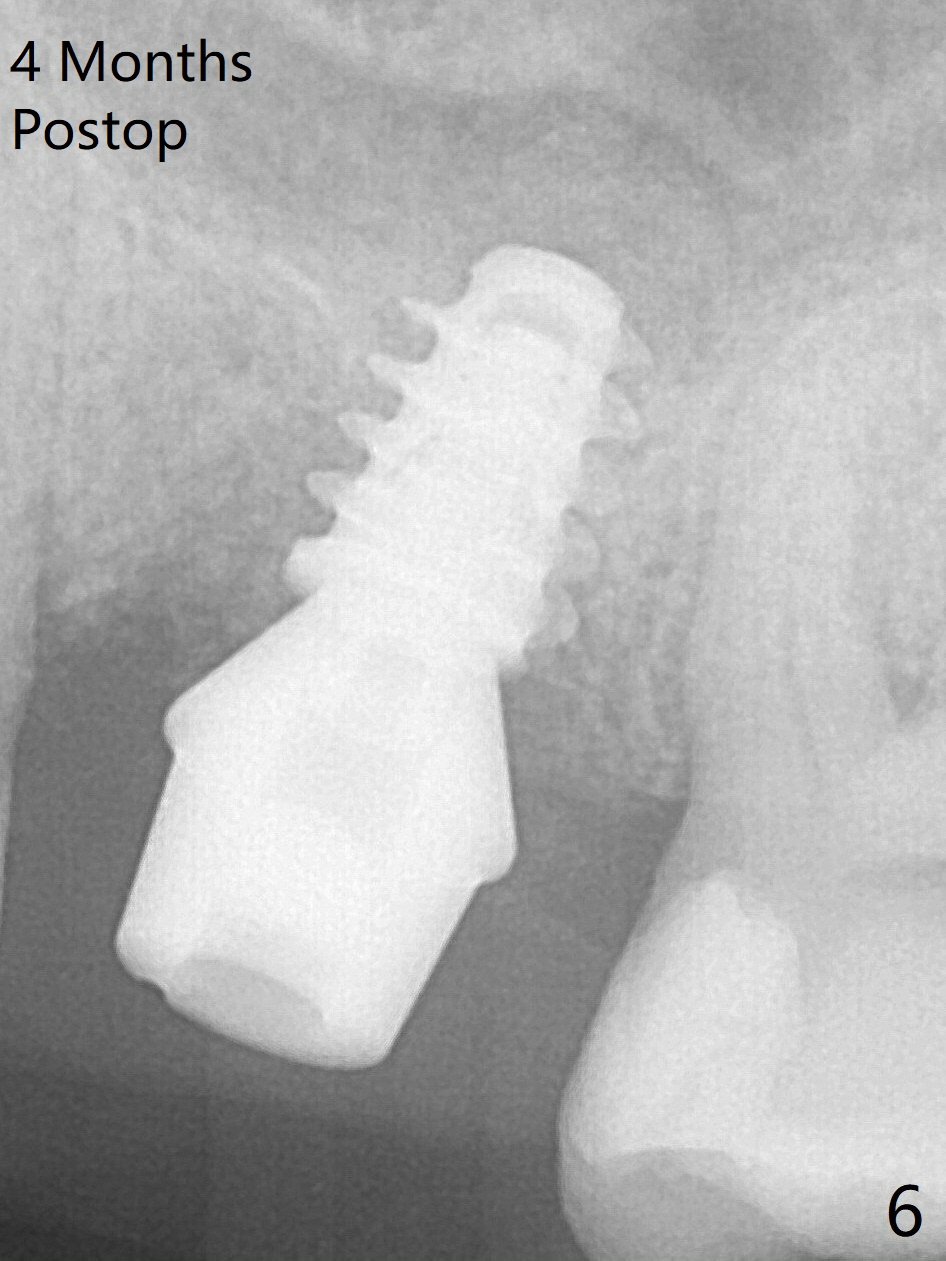

The implant is mobile 4 months postop (Fig.6).  A 6x2 mm healing abutment is placed next.  Although the implant remains mobile 6 months postop, the bone seems to have become denser around the implant (Fig.7-9).  A healing screw is placed.  When the bone height is limited (<7 mm), place a larger implant (>5.5 mm).  The implant seems to have osteointegrated 8 months postop (Fig.10).  Impression is taken following placing a 6.5x4(3) mm abutment.  The patient reports pain after cementation, which is less when the abutment screw is loose (9.5 months postop, 2 weeks post cementation).  CBCT taken after placement of a healing screw apparently shows loose bone mesial and distal to the implant (Fig.11 *).  The implant trajectory is less favorable.  It seems necessary to change to a large implant with more sold threads (Fig.12).